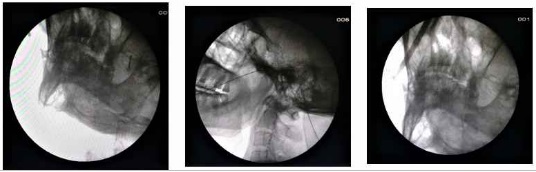

Η θερμοπηξία με ραδιοσυχνότητες (RFTC) είναι μια από τις πιο αποτελεσματικές και ασφαλείς θεραπευτικές πράξεις  ημερήσιας νοσηλείας. Γίνεται στο χειρουργείο υπό ακτινοσκοπική καθοδήγηση με τοπική αναισθησία και ήπια καταστολή. Προσφέρει 80 έως 90% ανακούφιση από τον πόνο, έχοντας ωστόσο ορισμένα μειονεκτήματα όπως, παράπονα του ασθενούς  για μούδιασμα ή  ασυνήθιστη αίσθηση στην περιοχή κατανομής του νεύρου στο πρόσωπο. Με τη μέθοδο αυτή μια βελόνα εισάγεται στο ωοειδές τρήμα στη βάση του κρανίου και μέσω αυτής εισέρχεται το ηλεκτρόδιο που χορηγεί την ενέργεια και καυτηριάζει το γάγγλιο του τρίδυμου νεύρου.